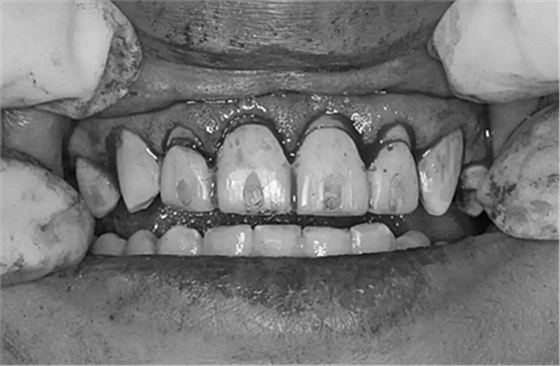

第5次復(fù)診的時(shí)候,終于讓我們4個(gè)兄弟恢復(fù)了正常的容顏。

現(xiàn)在剩下的任務(wù)就是為我其他的兄弟姐妹們治療了。需要做根管的做根管,需要做冠的做冠,需要樹脂充填的做樹脂充填。前前后后主人帶我們進(jìn)行了12次的復(fù)診,歷時(shí)6個(gè)月,現(xiàn)在的我們是這樣的